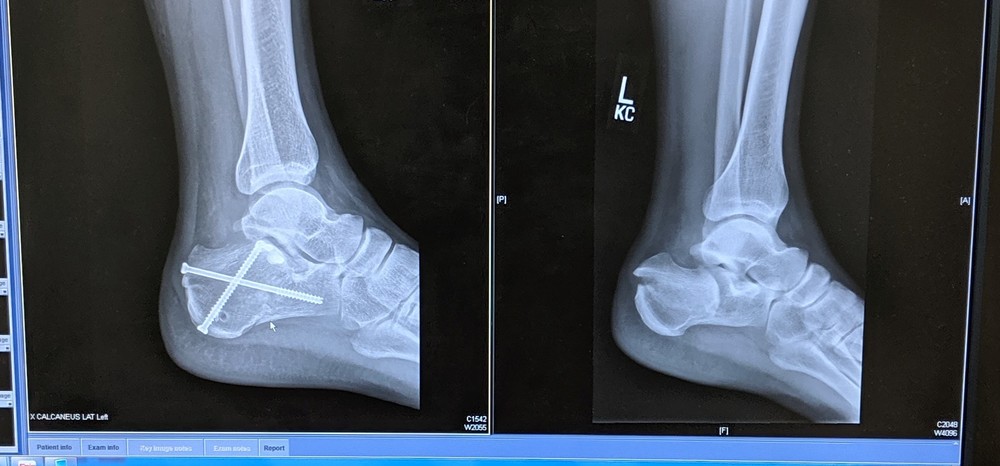

Still in recovery/rehab mode here, went twice to rehab place not much good news,so far, leg needs to come back more up (im minus 15 on it) left to right only little movement , still cant curl toes down, and im 1 week out from hard cast,the people at rehab they good but can only do so much.... now good news ,no pain in it and im putting about 60 to 70 % weight on it...Honestly i think the rehab is the hardest part in this injury, and how lucky you get...Thanks Steve,Jeff ,Bryan and now John for all the nfo Some pics from today, injured led wont come back like other one Some pics from today, (rehab people told me to use compression sock during the day) Before x-ray right when broken ,left after surgery. 2 weeks after surgery. |

I am a surgeon who performs this surgery and a lifer climber. happy to answer questions directly or even review xrays etc...Bottom line with this fracture is the damage to the cartilage and the joint and how well that can be put back together. if the joint isn't broken and alignment can be repaired, then return to active life is possible. Younger, healthier (people) joints fair best. The other challenge comes if there are other injuries/fractures sustained at same time further delaying recovery. Bone takes 6 wks to heal and most people take 6-12 months to total rehab. |

these extra entry points are true stab incisions where we put big pins into the bigger chunks of bone to toggle, joystick the fracture back in position. |